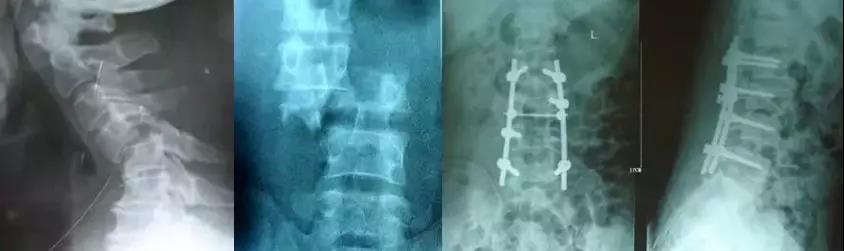

1)脊柱骨折/脱位

- 生命体征平稳,骨折移位较大,有神经症状,应紧急手术;

- 最迟1周之内。